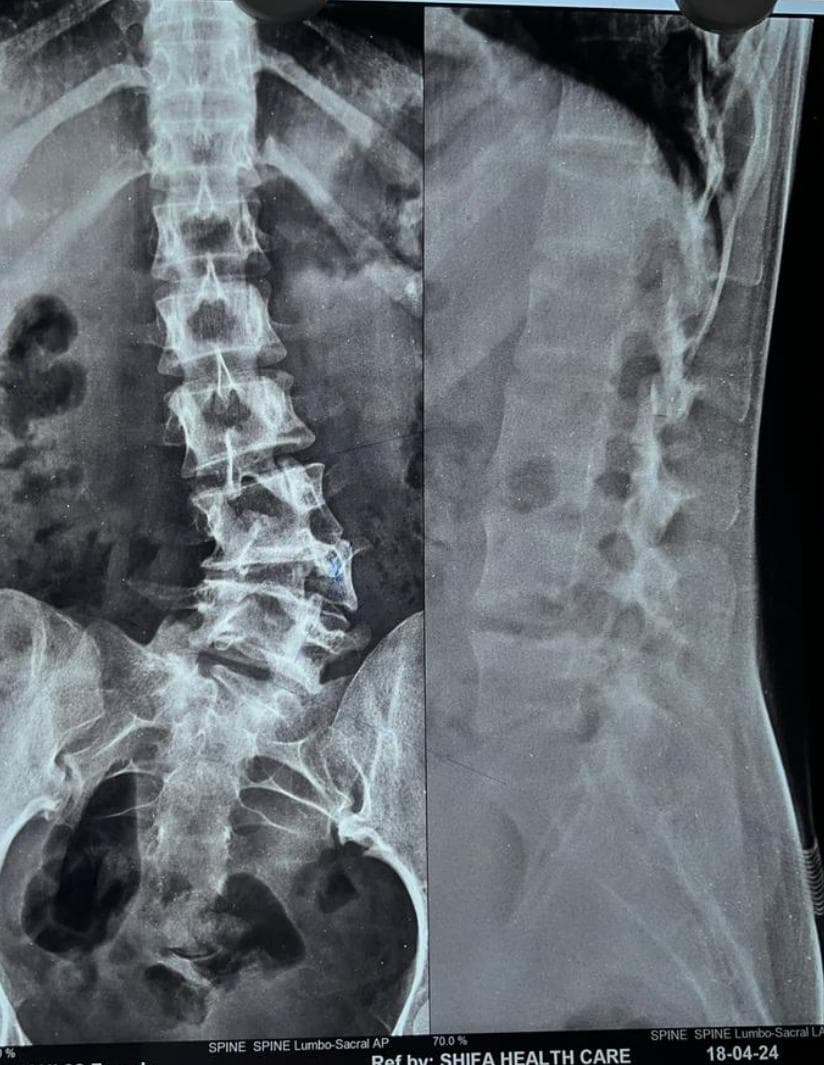

A hemivertebra is a wedge-shaped vertebra that disrupts the normal alignment of the spine, often resulting in progressive scoliosis. When left untreated, especially in growing children and adolescents, the curvature tends to worsen with age, leading to severe spinal imbalance, chronic pain, restricted lung function, and psychosocial challenges.

In this patient’s case, the hemivertebra at L4 created a significant lumbosacral curve that affected the natural biomechanics of the spine, causing pain, a tilted posture, and aesthetic concerns.

After thorough evaluation and counseling, Dr. Bhupendra Pratap Bharti , a leading spine deformity correction specialist, recommended surgical correction to prevent further progression of the curve and relieve her symptoms.

The chosen surgical approach was:

This approach was chosen for its effectiveness in correcting deformity while preserving spinal mobility, especially important in a young and active patient.